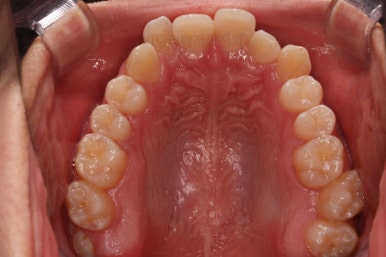

종료 시의 사진들을 전후 비교해 보겠습니다.

입매가 좋아졌고 입을 다무는 편안함도 좋아졌으며 치열이 가지런해졌으며 웃을 때 보이는 치열의 느낌도 좋고 교합도 잘 마무리 되었네요.

지켜봐도 되는 충치는 지켜보기로 여지를 남기고 필요한 충치치료도 마무리를 했습니다.